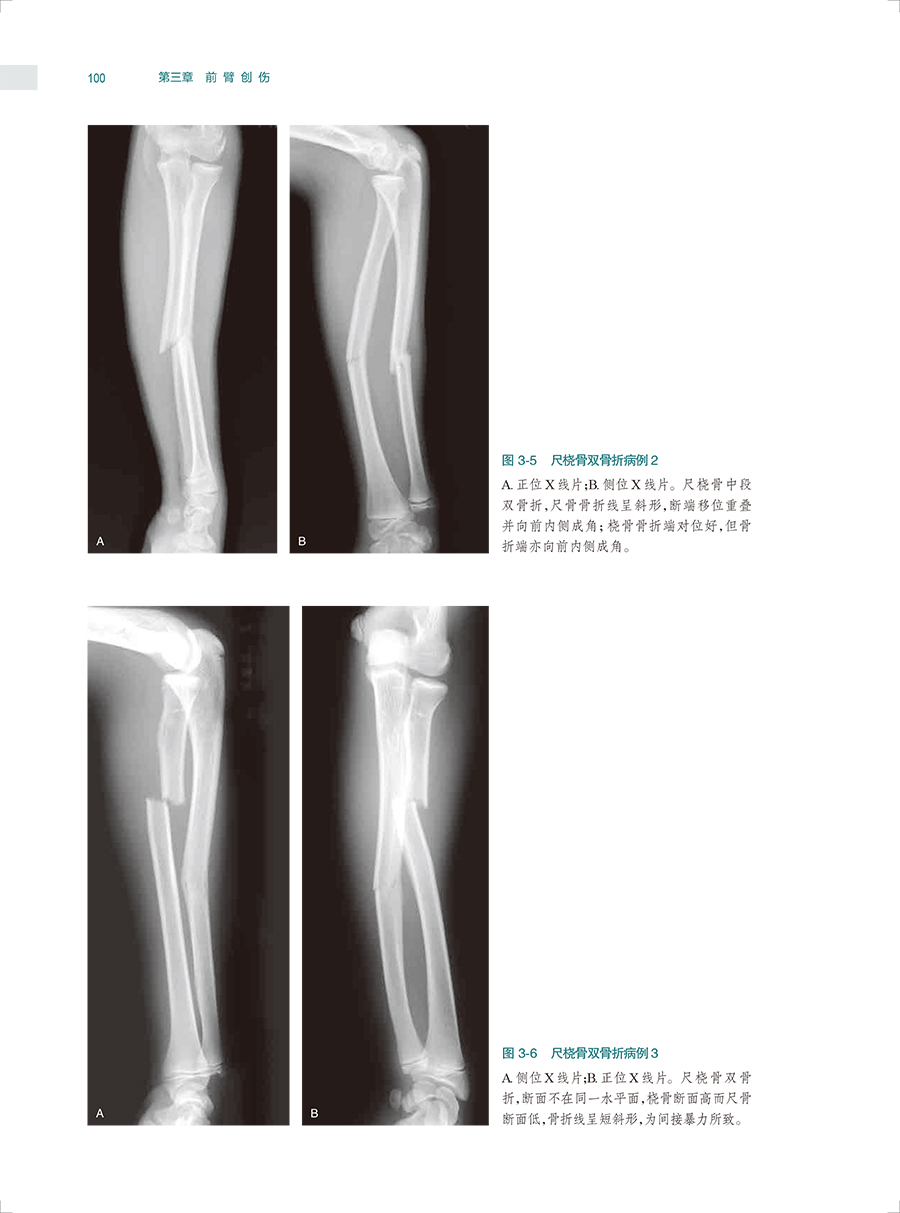

本书是一本系统全面介绍骨关节创伤X线诊断的图谱专著。全书共十六章,前十五章每章基本按创伤类型、诊断要点和鉴别诊断体例编写,最后一章介绍常见骨关节创伤后遗症及并发症。书中共选用1270幅X线照片图,约760个病例,所选图片和病例均具有代表性,可使读者对各部位、各类型的骨关节创伤及其后遗症和并发症有进一步认识,从而提高诊断水平。本书主要供骨科医生、影像科医生使用。